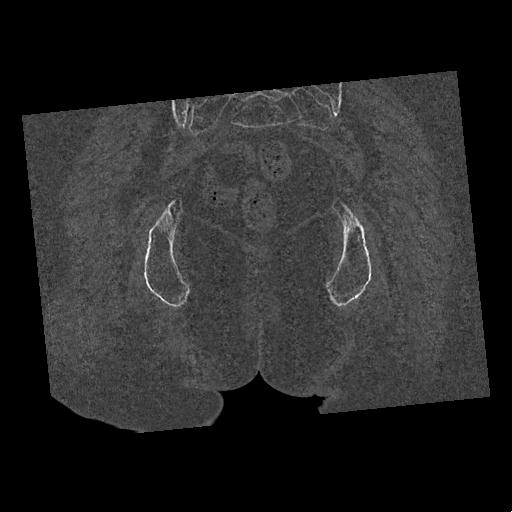

100703 1/27 両股正面+軸 1/29 両股正面+軸 94歳女性 パンソンロン